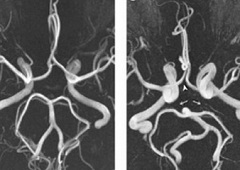

При проведении окулистом был поставлен диагноз: Гиперметропия слабой степени, нисходящая частичная атрофия зрительного нерва.. При проведении серии МР ангиограмм, выполненных в режиме TOF в аксиальной проекции с последующей обработкой выявлено следующее: внутренние сонные артерии имеют нормальный диаметр, расположены симметрично. Сифоны ВСА выражены отчетливо, без признаков компрессии. Отмечается извитость хода обеих ВСА.

Средние мозговые артерии и передние мозговые артерии отходят с каждой стороны от ВСА, не изменены.

Вариант развития Виллизиева круга в виде отсутствия кровотока по обеим задним соединительным артериям.

Основная артерия имеет обычный ход и диаметр и разделяется на задние мозговые артерии, которые имеют обычный диаметр.

Определяется сужение просвета и снижение кровотока по интракраниальному отделу правой ПА.